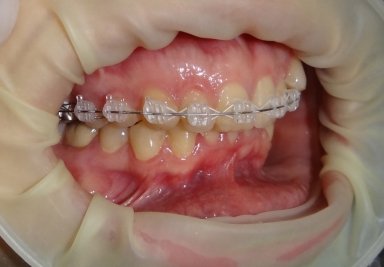

Sapphire orthodontic device

Orthodontic treatment, external sinus lifting.

Orthodontic treatment

full ceramic crowns and veneer